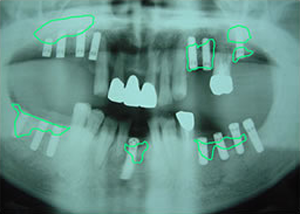

症例4 57歳女性

2009 6/21 更新

治療前

(下11本、上1本抜歯済み)

平成19年6月29日

1.・骨つくり

・インプラント15本埋入

ソケットリフト

サイナスリフト

リッジオギュメンテーション